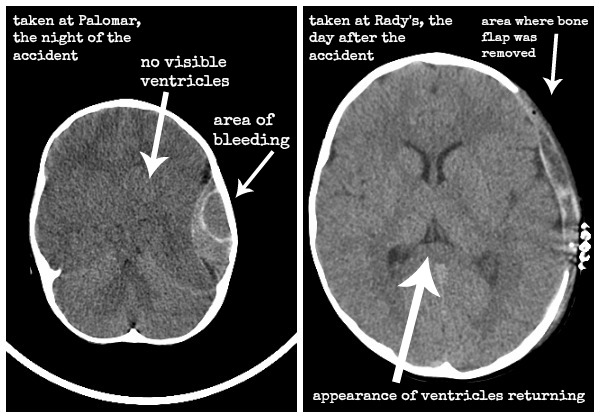

The morning of January 12th, the “team” involved with Simon had a meeting that we were included in to review his records and discuss their plan for us in rehab. Because Jesse was working, my mom attended with me. It was quite strange to be the parent at the meeting, while I’m usually on the therapist side of things. I remember how, during most of the meeting, thinking how weird it was that I was a parent, especially since I feel so young mentally, even though I was thirty years old. All of the therapists commented that they were extremely happy with the progress Simon was making and didn’t plan on us being there very long. Our rehab doctor, Dr. Skalsky, reviewed Simon’s CT scans from when we were at Palomar Hospital (hours after the accident) and the ones they took the next day after the surgery. It was incredible to see how “squished” his ventricles were with all of the bleeding that he sustained. It was truly a miracle that he was alive and not brain dead.